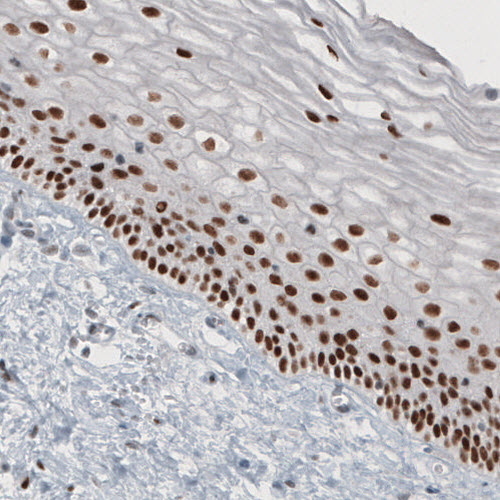

Immunohistochemical staining of human cervix shows strong nuclear immunoreactivity in epithelial cells.